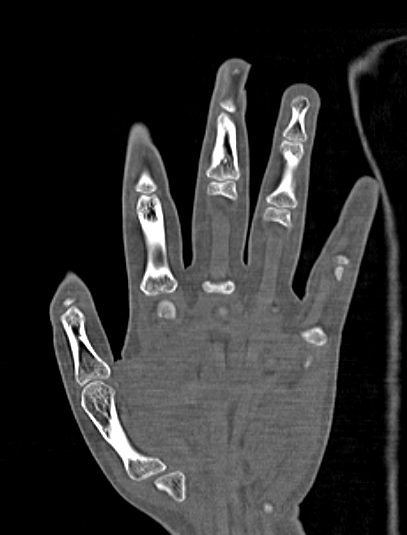

Кисти рук имеют сложное анатомическое строение. Кисть состоит из трех отделов:

- запястье (образовано 8-ю костями), которое участвует в формировании лучезапястного сустава;

- пясть (состоит из 5 трубчатых пястных костей);

- пальцы рук (состоят из 2 или 3 мелких трубчатых костей, соединенных межфаланговыми суставами).

В структуре кисти кроме большого количества мелких костей присутствует множество связок, мышц и сухожилий. Кисть хорошо кровоснабжается и имеет развитую иннервацию. Благодаря такому анатомическому строению кисть обладает гибкостью и высокой подвижностью, что позволяет совершать большое количество точных координированных движений. Любые патологические процессы, нарушающие функцию кистей рук, ведут к инвалидизации человека, снижая его способность к самообслуживанию и трудовой деятельности.

Метод мультиспиральной КТ основан на использовании ионизирующего излучения, которое используется для послойного сканирования внутренних структур организма. Благодаря тончайшим срезам и последующей цифровой обработке полученных данных получаются послойные снимки и 3D-изображения кистей рук в мельчайших подробностях.

В наших диагностических центрах установлены современные мультиспиральные компьютерные томографы последнего поколения TOSHIBA AQUILION. Аппараты послойно сканируют исследуемую область с шагом от 0,5 мм, делая за считанные секунды снимки высокой четкости и контрастности. Высокая скорость сканирования дает минимальную дозу рентгеновского облучения для пациента, при этом обеспечивается точность и достоверность диагностики различной патологии.

Наиболее распространенной причиной диагностической процедуры является травматическое повреждение. Переломы мелких костей на рентгенограмме зачастую могут визуализироваться неотчетливо за счет наложения костных структур друг на друга, а компьютерная томография позволяет различать все кости отдельно и является «золотым стандартом» для исключения повреждения костей.

Компьютерная томография лучше всего подходит для обследования костных структур, так как кости в большей степени поглощают рентгеновские лучи и поэтому хорошо видны на снимках. Для того, чтобы улучшить визуализацию мягких тканей, дополнительно проводится контрастное усиление. Обычно это применяется при подозрении на развитие опухолевых образований.